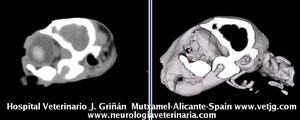

Click aquí para ver reconstrucciones en 3D a partir de imágenes de TC |

Mismo paciente: Correspondencias entre el corte sagital y el volumen, ambos reconstruidos a partir de imágenes TC (transversales) |